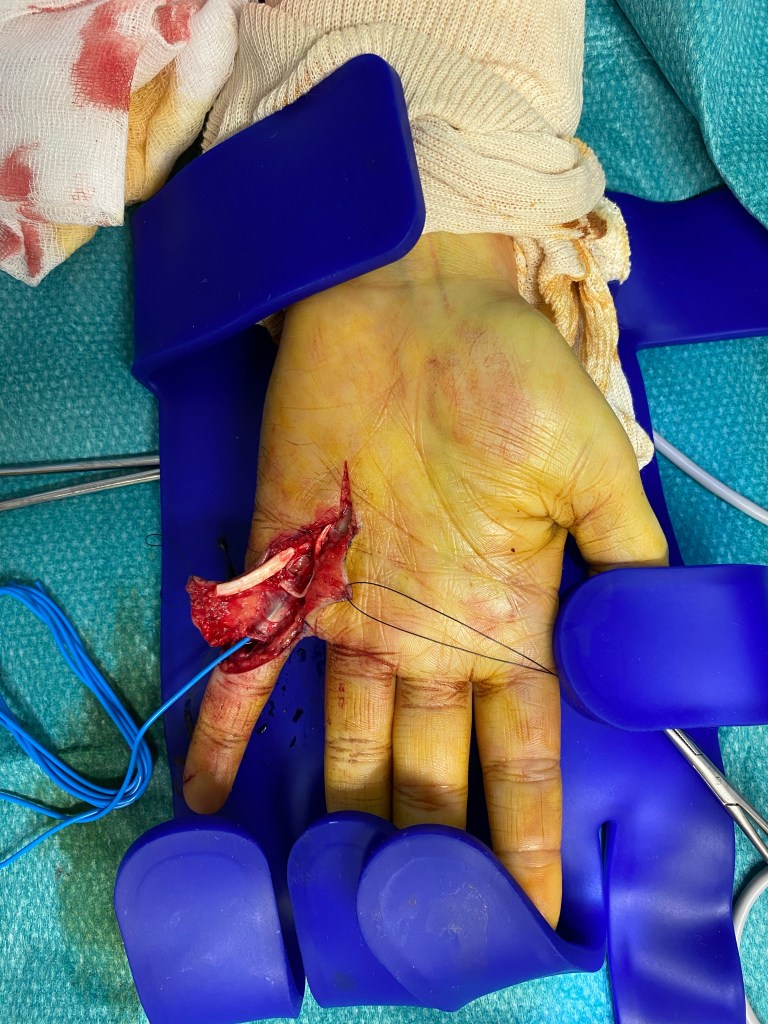

L’exploration d’une plaie consiste à rechercher des lésions des structures profondes et/ou des corps étrangers.

Elle peut être rendue nécessaire pas le caractère profond ou souillé de la plaie , des signes cliniques (saignement important , absence de sensibilité d’une zone) ou par la localisation de la plaie (la main est particulièrement riche en tendons nerfs et vaisseaux).

Pour cela, il est possible et fréquent que la plaie soit agrandie, afin de réaliser une vérification exhaustive.